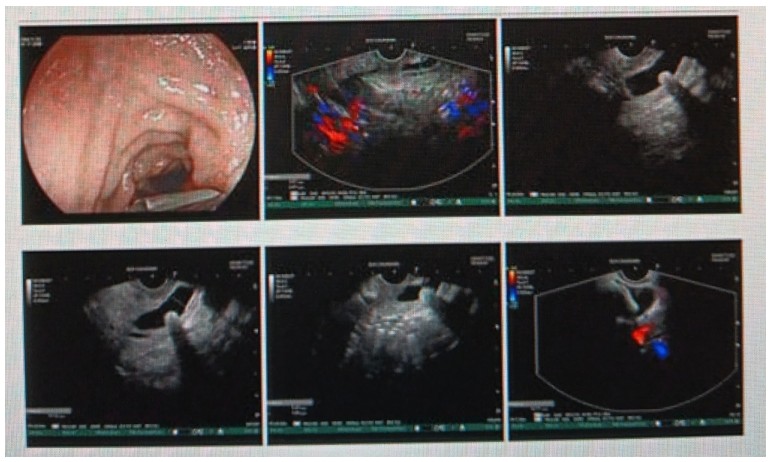

消化內(nèi)科肝病亞專科團(tuán)隊(duì)詳細(xì)討論,分析患者情況后,取消了周女士的肝穿刺活檢檢查,建議患者先行超聲胃鏡下膽胰掃查。在內(nèi)鏡醫(yī)師第三只眼——超聲胃鏡的掃查下,發(fā)現(xiàn)引起周女士肝功能受損的罪魁禍?zhǔn)?/span>原來是膽總管末端結(jié)石!伍友興主任醫(yī)師帶領(lǐng)團(tuán)隊(duì)給予患者行ERCP下取石后,周女士未再出現(xiàn)腹痛,肝功能恢復(fù)正常。

無獨(dú)有偶,劉先生也為反復(fù)出現(xiàn)肝功能受損到多家醫(yī)院就診檢查,未能找到原因,來到衡陽市中心醫(yī)院消化內(nèi)科就診,希望能在肝穿刺活檢下得出病因。在行肝穿刺活檢之前,醫(yī)生建議劉先生行超聲胃鏡膽胰掃查,發(fā)現(xiàn)引起劉先生反復(fù)肝功能受損原因,亦是膽總管結(jié)石引起,在ERCP術(shù)取石術(shù)后,患者肝功能恢復(fù)正常,未再出現(xiàn)異常情況。

張丹霞主任醫(yī)師介紹,超聲內(nèi)鏡通過胃十二指腸自然腔道,可以將探頭貼近相應(yīng)的位置,近距離的觀察胰腺及膽道系統(tǒng),準(zhǔn)確捕捉到直徑小于5毫米的胰腺異常病灶及膽道系統(tǒng)病灶。而體表B超常受皮膚、脂肪或腸道氣體干擾。CT或磁共振檢查只能提供靜態(tài)圖像,且對膽胰管陰性結(jié)石或是未引起明顯膽管梗阻性的結(jié)石檢查有局限性,因此對于有輕微腹痛合并肝功能受損的患者,建議常規(guī)行超聲胃鏡下膽胰掃查。超聲胃鏡、腹部彩超、腹部CT、腹部MRI同為診斷膽管細(xì)微病變的四架馬車,在膽總管結(jié)石診斷方面,超聲胃鏡膽胰掃查同ERCP一樣,是敏感性高、特異性強(qiáng)的診斷方法。超聲胃鏡發(fā)現(xiàn)可疑病變,可以完成穿刺活檢,還可行囊腫穿刺引流、膽管減壓、消融術(shù)等。